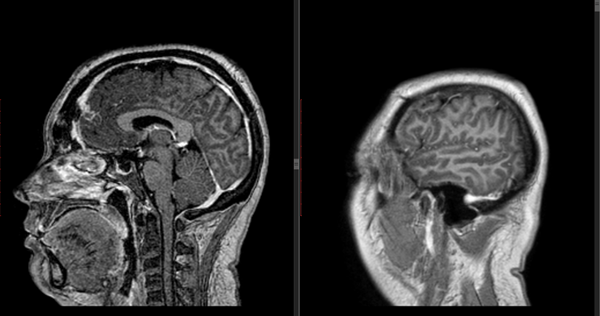

Figura 1: RM en secuencia T1 cortes a) 1axial, se observa lesión espontáneamente hiperintensa y su relación con vasos del polígono de Willis. b) RM en secuencia T1 corte sagital, donde se observa extensión supraselar de la lesión comprimiendo lamina terminalis

Figura 6: RM cortes axiales en T1 evidenciando ausencia de lesión tumoral.

Figura 7: RM T1 con gadolinio cortes sagital y coronal que evidencian ausencia de lesión tumoral.